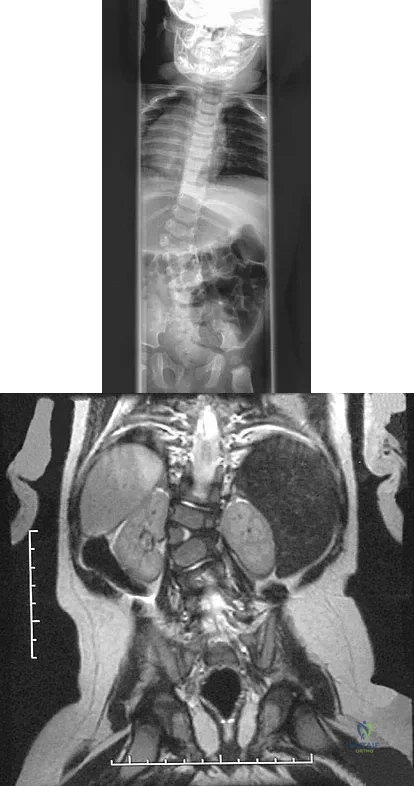

A 5-year-old girl sustained a comminuted Salter-Harris type IV fracture of the left distal tibia 2 years ago. The AP radiograph shown in Figure 54a reveals a growth arrest and a 1.4-cm limb-length discrepancy. The ankle is in approximately 20 degrees of varus. Figure 54b shows a coronal reconstruction image of the distal tibial physis, and Figure 54c shows a sagittal reconstruction image of the same area. On the sagittal reconstruction image, the bar extends from the 9-mm mark to the 24-mm mark in 3-mm increments. On the coronal image, the bar extends from the 9-mm mark to the 24-mm mark, also in 3-mm increments. A map of the physeal bar based on these measurements is shown in Figure 54d. Initial treatment should consist of